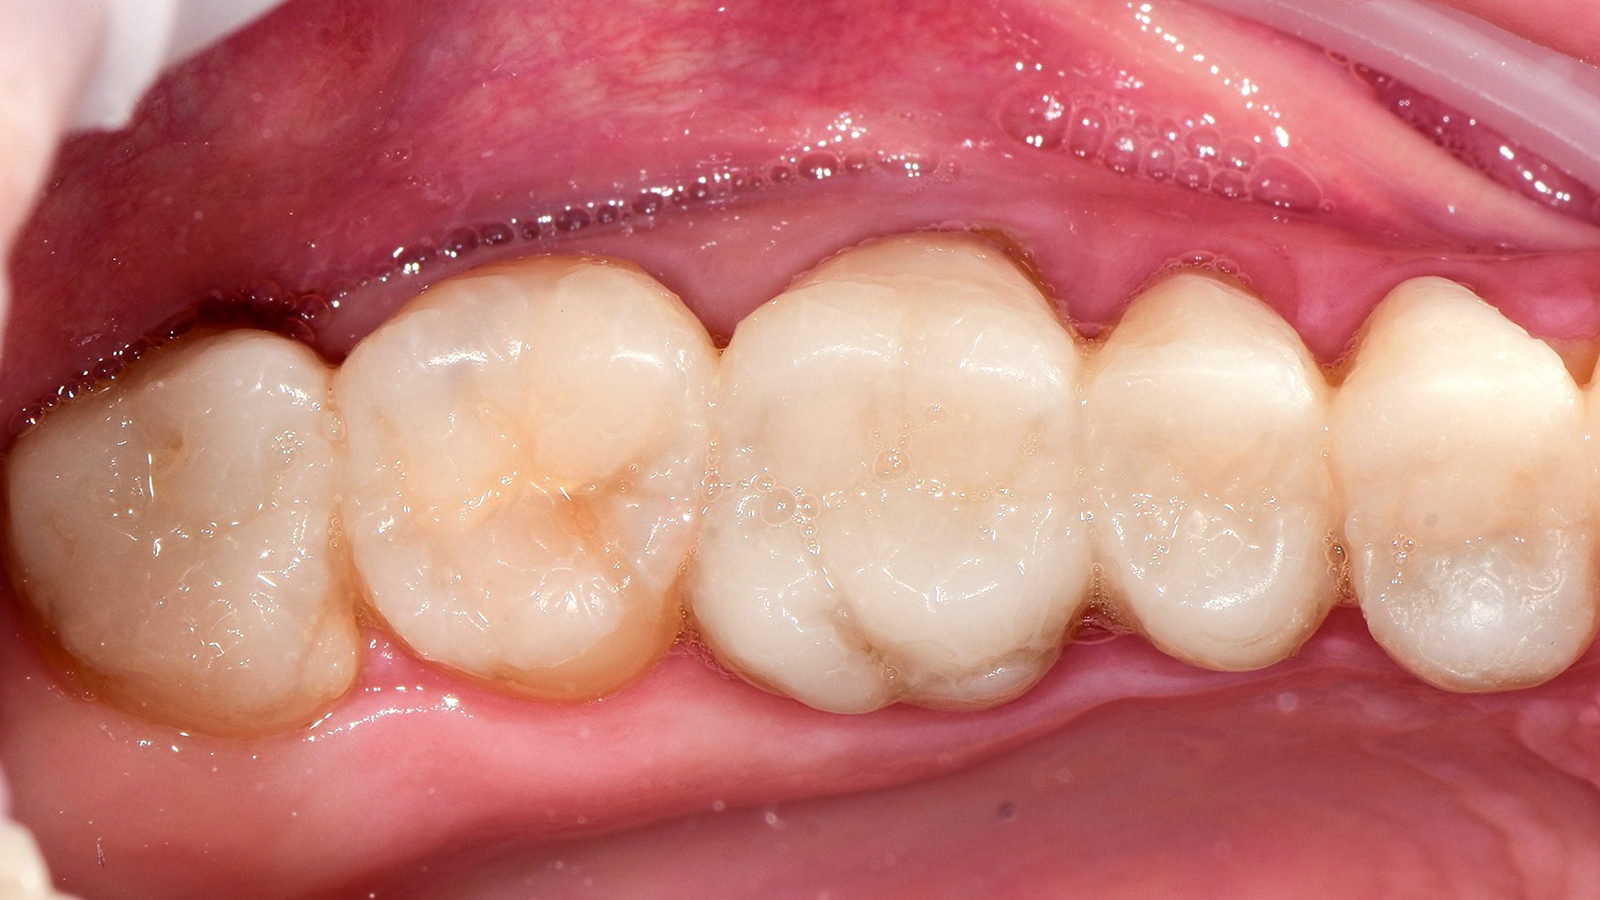

Charisma Diamond/ Charisma Topaz ONE Shade blends seamlessly into the surrounding dentition, independent of the tooth shade, enabling restorations to simply disappear. The universal composites for everyday restorations offer a new one-shade solution within the Charisma family for the majority of everyday cases.

Charisma Diamond/Charisma Topaz ONE Shade determines the shade of the restoration by absorbing the lightwaves that are reflected by the surrounding tooth shade.

The ONE shade has been optimised to deliver the perfect balance of chroma and translucency that allows the restoration to become virtually invisible. Therefore, the ONE shade can be used with confidence in any Class I and Class II restoration. And this colour adaptation is what we call Adaptive Light Matching.